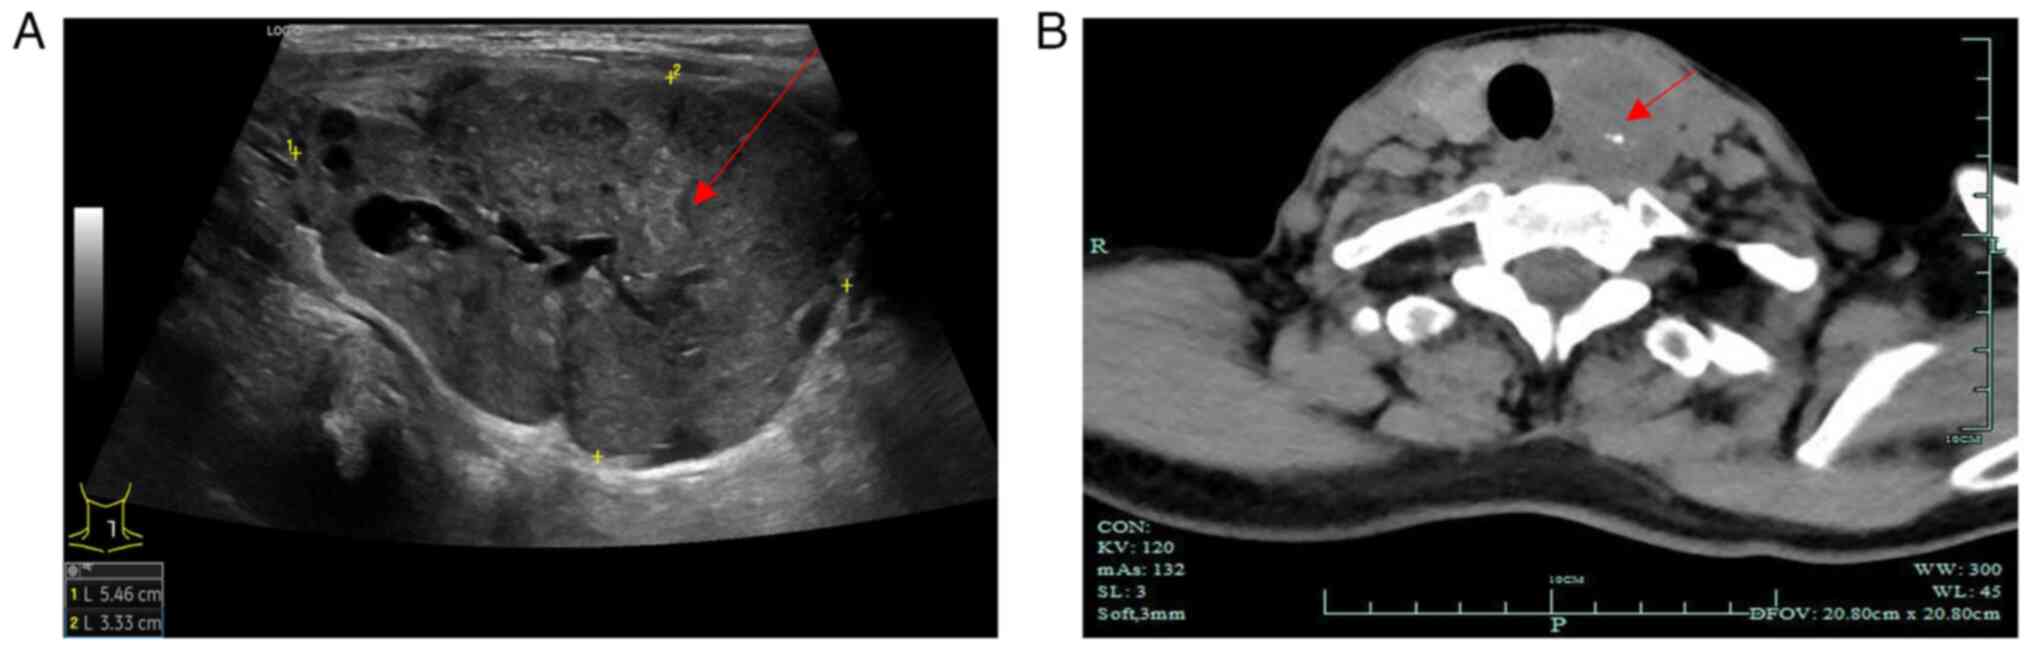

In April 2023, a 60-year-old female was referred to Ningbo Beilun District People's Hospital (Ningbo, China) with radiographic findings indicating thyroid nodules. The previous medical history of the patient included a left radical nephrectomy in February 2021, performed for the treatment of ccRCC. Histological examination revealed grade 1 ccRCC (23), and no other distant metastases were observed during follow-up. As shown in Fig. 1A, preoperative thyroid ultrasound examination results indicated a hypoechoic nodule in the left lobe of the thyroid [Thyroid Imaging Reporting and Data System (TI-RADS) 4a] and a nodule in the right lobe of the thyroid (TI-RADS 3). TI-RADS is a classification level for thyroid nodules, where TI-RADS 4a indicates the presence of one of the following ultrasonographic malignant features: Extremely hypoechoic, microcalcifications or irregular microlobulated margins; the probability of malignancy in this category ranges from 5 to 10% (24). The results of computed tomography revealed enlargement of the left lobe of the thyroid with a mass-like low-density shadow inside, measuring ~40×32 mm (Fig. 1B). In addition, the left lobe exhibited poorly defined borders and an uneven density with visible calcifications inside the mass (Fig. 1B). Multiple small nodules were observed in the right lobe of the thyroid, with no abnormal density shadows observed in the isthmus of the thyroid. Notably, the patient did not present with enlarged lymph nodes on either side of the neck. The results of urine and blood tests were normal, and normal functioning of the thyroid and parathyroid was observed. Given the large size of the mass, there was a risk of tracheal deviation and compression. The patient's history of ccRCC and the potential for malignancy in the thyroid nodules was considered, and after the patient was informed, they refused fine needle aspiration cytology and opted for total thyroidectomy.

Figure 1.

Ultrasound and computed tomography imaging of the thyroid. (A) Ultrasonography revealed a well-defined, hypoechoic mass (red arrow) with microcalcification, measuring 55×41×33 mm in the left lobe of the thyroid gland. (B) Computed tomography demonstrated that the left lobe of the thyroid gland was enlarged, with a mass-like area of low density (red arrow), measuring ~40×32 mm. Tumor density was heterogeneous with visible calcifications.